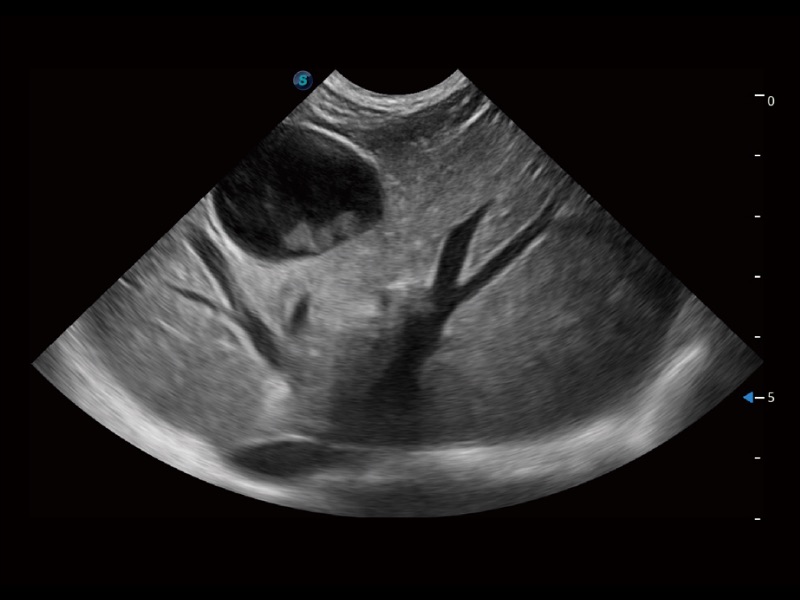

ProPet 70 进一步提升了微米成像算法,更加注重对基础原始图像的还原和保留,在有效减少斑点噪声、增强组织边界显示的同时,避免过度优化丟失真实的解剖信息。

通过创新的 Matrix E自适应滤波器和超长时间域算法,极大提升超低速微细血流的检出能力,同时更精准地滤除软组织和噪声信号,为兽用医生提供以往无法通过常规血流获得的疾病诊断信息。

通过色彩血流和实时宽景相结合,可观察到完整的静脉或动脉的血流,方便医生检查。实时扫查过程中,如有任何操作失误也可以很容易地进行回扫擦除,而不会中断扫查。